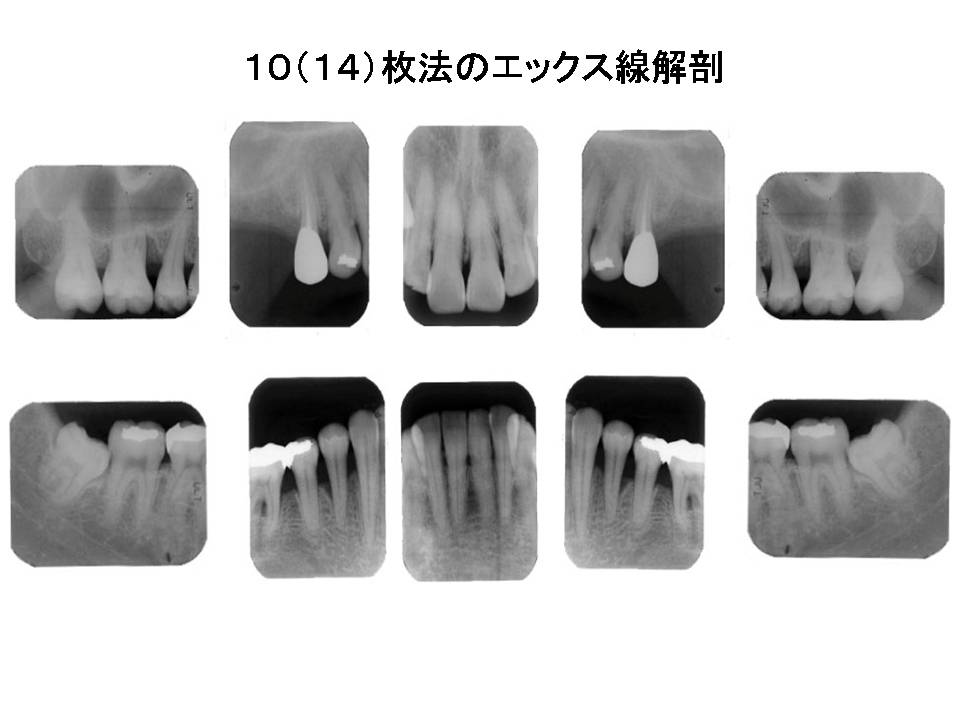

口内法(二等分法・咬合法)撮影の解剖